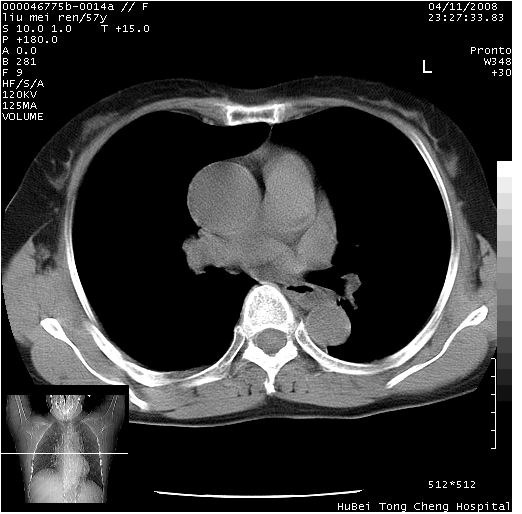

患者 女,57岁。因车祸受伤,其家属要求行“全身ct检查”。平素健康。

胸部ct轴位平扫(层厚10mm,螺距1.5,重建间隔10mm),图像如下:

上腔静脉变异

左位上腔静脉,先天变异。

左位上腔静脉,先天变异。与双侧上腔静脉区别。